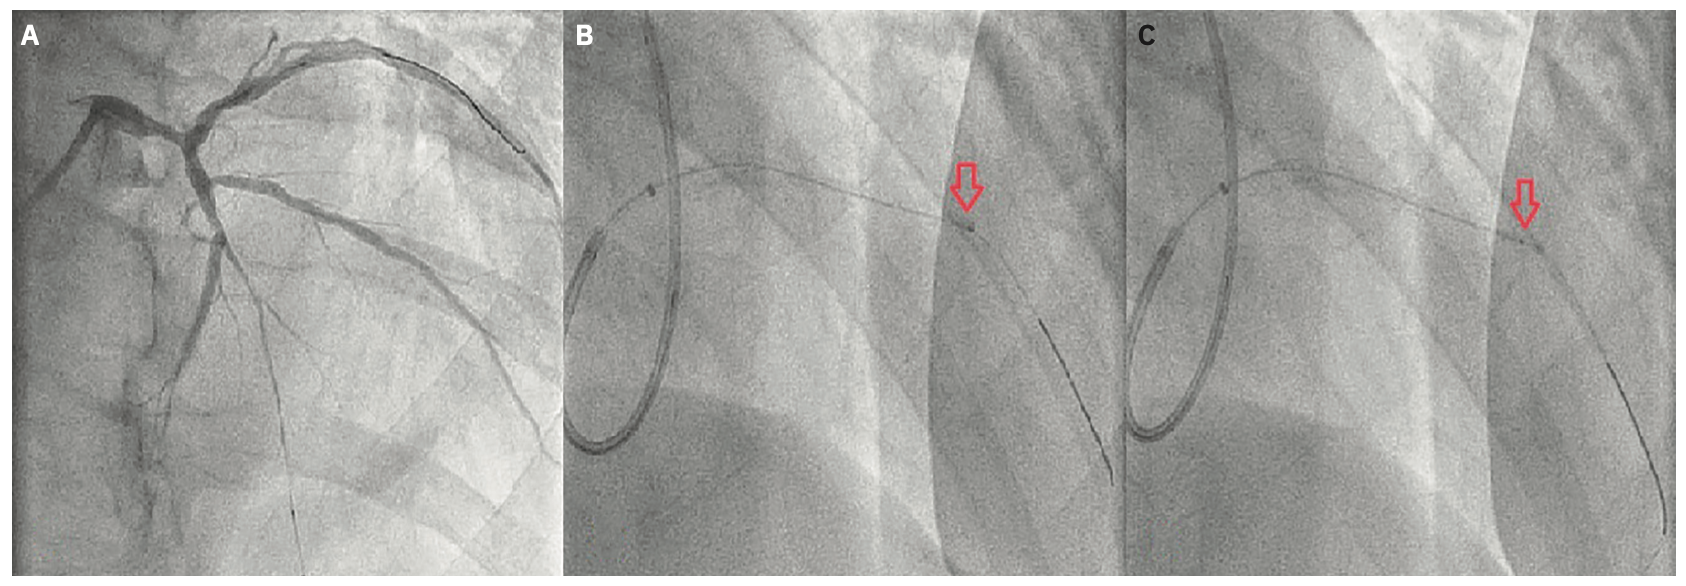

A 65-year-old male presented with a few days of productive cough, progressive fatigue, worsening scrotal edema, and high-grade fever. His past medical history included essential hypertension, tobacco abuse, ischemic cardiomyopathy with a left ventricular ejection fraction (LVEF) of 20%, and severe multivessel coronary artery disease (CAD) involving the left main (LM) (80%), mid left anterior descending artery (LAD) (100%), and distal right coronary artery (RCA) (90%). Vital signs at presentation were notable for hypotension and sinus tachycardia. Physical exam showed 2+ pitting edema of the lower extremities, significant scrotal edema, and inspiratory and expiratory wheezes on auscultation. Laboratory test results were notable for troponin elevation of 0.12 ng/mL and BNP of 7722 pg/mL. Creatinine was elevated at 1.74 mg/dL, which was above the patient’s baseline. An electrocardiogram (EKG) showed inferior Q waves, widespread T wave abnormalities, a right bundle branch block, and a left posterior fascicular block (Figure 1). The chest x-ray showed cardiomegaly without pulmonary infiltrates/consolidation. An echocardiogram showed a severely enlarged left ventricle with a left ventricular ejection fraction of 15%-20%. During his hospital stay, the patient developed cardiogenic shock requiring short-term inotropic support with dobutamine. After stabilization, the patient underwent a coronary angiogram, which showed progression of his CAD with a 90% distal LM stenosis, mid-LAD chronic total occlusion (CTO), and a 99% distal RCA lesion. In the past, the patient had elected not to pursue invasive management and was treated only medically. This time, the patient was willing to consider any treatment option, so cardiothoracic surgery was consulted. The patient was not found to be a good candidate for surgical revascularization. Before discharge, the patient underwent successful percutaneous coronary intervention (PCI) of the RCA with drug-eluting stent (DES) placement. Two weeks later, he presented for staged PCI of the LAD CTO. For the procedure, right radial access was utilized. Dual access was not obtained due to the absence of significant right-to-left collaterals. The LM ostium was engaged with a 6 French Launcher Extra Backup (EBU) 3.5 guide catheter (Medtronic). Initially, the procedure proceeded according to the plan. We were able to cross the LAD CTO without significant difficulties using a Prowater .014-inch, 180 cm coronary guide wire (Abbott Vascular) (Figure 2A). Unfortunately, we were unable to advance further interventional equipment into the lesion. Eventually, we managed to partially insert a semi-compliant balloon into the proximal end of the stenotic area. At this point, with two-thirds of the Sprinter Legend Rx 1.5 mm x 6 mm balloon (Medtronic) still proximal to the lesion, we elected to go forward with the technique of controlled balloon explosion (Figure 2B). Eventually, balloon rupture (Figure 2C) occurred at a pressure of 20 atmospheres. The following angiogram showed a dissection in the LAD, an expected finding with this technique (Figure 3A). After the successful lesion modification, we advanced a 2.0 mm x 20 mm Euphora Rx balloon (Medtronic) for the purpose of post dilatation. Subsequently, a 2.5 mm x 34 mm Resolute Onyx (Medtronic) drug-eluting stent was successfully placed (Figure 3B). The remainder of the procedure was uneventful. For his LM disease, the patient successfully underwent staged high-risk PCI. A repeat echocardiogram after 3 months showed an improved EF at 25%-30%.